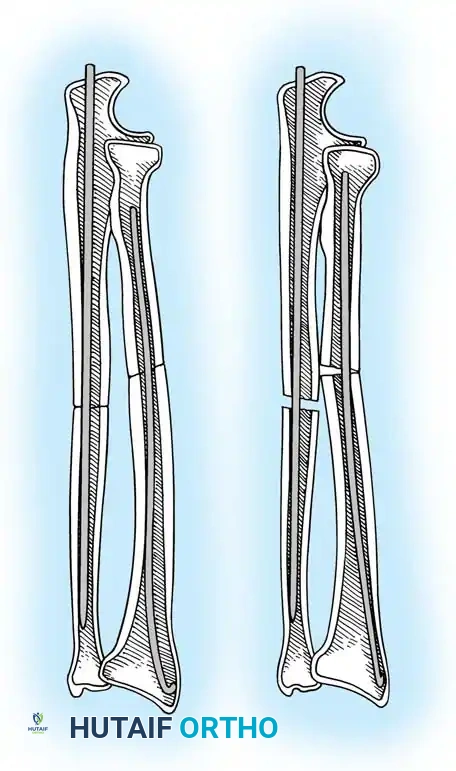

2. Intramedullary Fixation with Tension Band

If the fracture is more distal, or if there is a tendency for the proximal fragment to angulate posteriorly, a simple tension band wire is insufficiently stable. In these cases, intramedullary fixation (using Kirschner wires or a large cancellous screw) is combined with the tension band.

Kirschner Wires vs. Cancellous Screws:

* K-wires: The AO technique utilizes two parallel K-wires (1.6 mm or 2.0 mm) driven down the medullary canal. To prevent proximal migration, the K-wires must engage the anterior cortex of the ulna distal to the coronoid.

* Cancellous Screw: A biomechanical analysis by Murphy et al. demonstrated that a long 6.5-mm or 7.3-mm AO cancellous screw combined with a figure-of-eight wire provides a significantly stronger construct than K-wires. The screw must be long enough to achieve secure purchase in the ulnar diaphysis.

🔪 Surgical Technique: K-Wire and Tension Band (AO Technique)

- Reduction: Anatomically reduce the fragments and hold them temporarily with a reduction clamp.

- K-Wire Insertion: Introduce two parallel K-wires longitudinally from the tip of the olecranon across the fracture site. Direct them slightly anteriorly so they engage the anterior ulnar cortex distal to the coronoid process.

- Wire Loop: Pass an 18-gauge wire through a transverse drill hole in the distal fragment. Cross the wire in a figure-of-eight fashion over the posterior surface.

- Proximal Capture: Pass the wire around the protruding proximal ends of the K-wires.

- Double Twist: Weber and Vasey suggest twisting both limbs of the figure-of-eight loop. This double-twist modification ensures uniform compression across the fracture site.

- Securing K-wires: Bend the proximal ends of the K-wires 180 degrees, cut them short, and tap the bent ends deep into the triceps insertion and proximal bone to prevent symptomatic hardware prominence and migration.